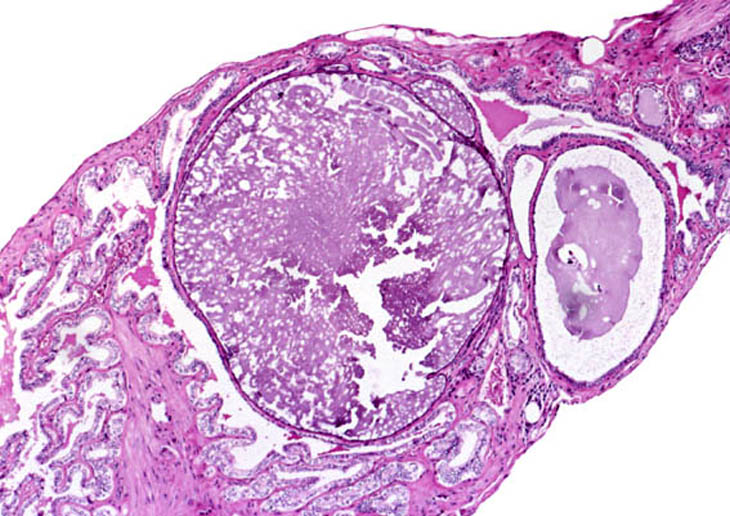

Cysts in the wall of the gallbladder.